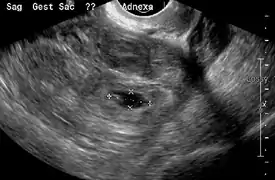

An ultrasound showing a gestational sac with fetal heart in the fallopian tube has a very high specificity of ectopic pregnancy. Transvaginal ultrasonography has a sensitivity of at least 90% for ectopic pregnancy.[4] The diagnostic ultrasonographic finding in ectopic pregnancy is an adnexal mass that moves separately from the ovary. In around 60% of cases, it is an inhomogeneous or a noncystic adnexal mass sometimes known as the "blob sign". It is generally spherical, but a more tubular appearance may be seen in case of hematosalpinx. This sign has been estimated to have a sensitivity of 84% and specificity of 99% in diagnosing ectopic pregnancy.[4] In the study estimating these values, the blob sign had a positive predictive value of 96% and a negative predictive value of 95%.[4] The visualization of an empty extrauterine gestational sac is sometimes known as the "bagel sign", and is present in around 20% of cases.[4] In another 20% of cases, there is visualization of a gestational sac containing a yolk sac or an embryo.[4] Ectopic pregnancies where there is visualization of cardiac activity are sometimes termed "viable ectopic".[4]

The combination of a positive pregnancy test and the presence of what appears to be a normal intrauterine pregnancy does not exclude an ectopic pregnancy, since there may be either a heterotopic pregnancy or a "pseudosac", which is a collection of within the endometrial cavity that may be seen in up to 20% of women.[4]